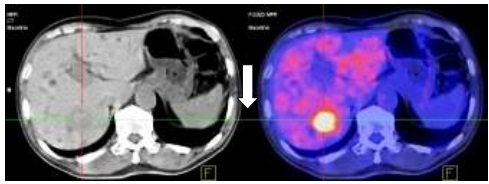

Hình 1.4. Di căn gan kích thước: 3x4cm, SUV=6,9.

Hình 2.6. Trước điều trị: U gan HPT VII KT: 3x4cm, SUV=7,4.

Hình 2.7. U gan phải sau hóa trị kích thước: 2x3cm, SUV=4,1.

Như vậy sau 6 chu kỳ hóa trị kết hợp Bevacizumab: Các tổn thương u nguyên phát, di căn hạch ổ bụng, nốt di căn phổi đã không còn, chất chỉ điểm khối u CA 19-9 giảm. Tuy nhiên tổn thương di căn gan vẫn tồn tại và kích thước tổn thương gan đã thuyên giảm còn 2x3cm.